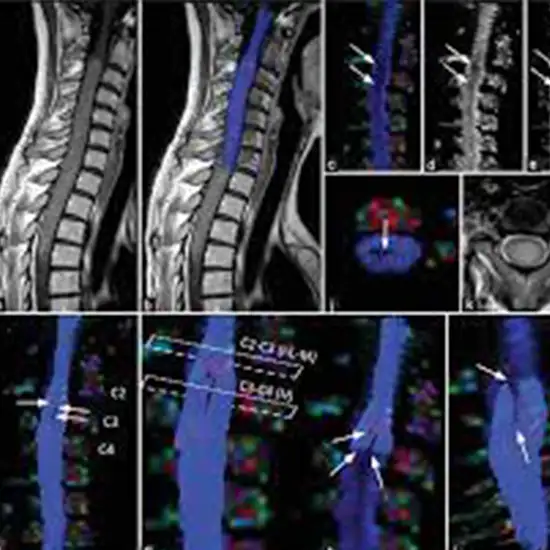

MRI Lumbar Spine with Tractography is an imaging procedure used in the early detection of lumbar spine injury and its severity. It is also recommended to get additional key details about the lumbar spine lesions. It is helpful in the effective treatment plan.

Doctors recommend MRI Lumbar Spine with Tractography to detect the lumbar spine injury and its severity. It is also used to get detailed information about lumbar spine lesions.  For planning the best treatment, doctors order this scan and compare the result with a conventional MRI to detect subtle pathological changes in the lumbar spine.